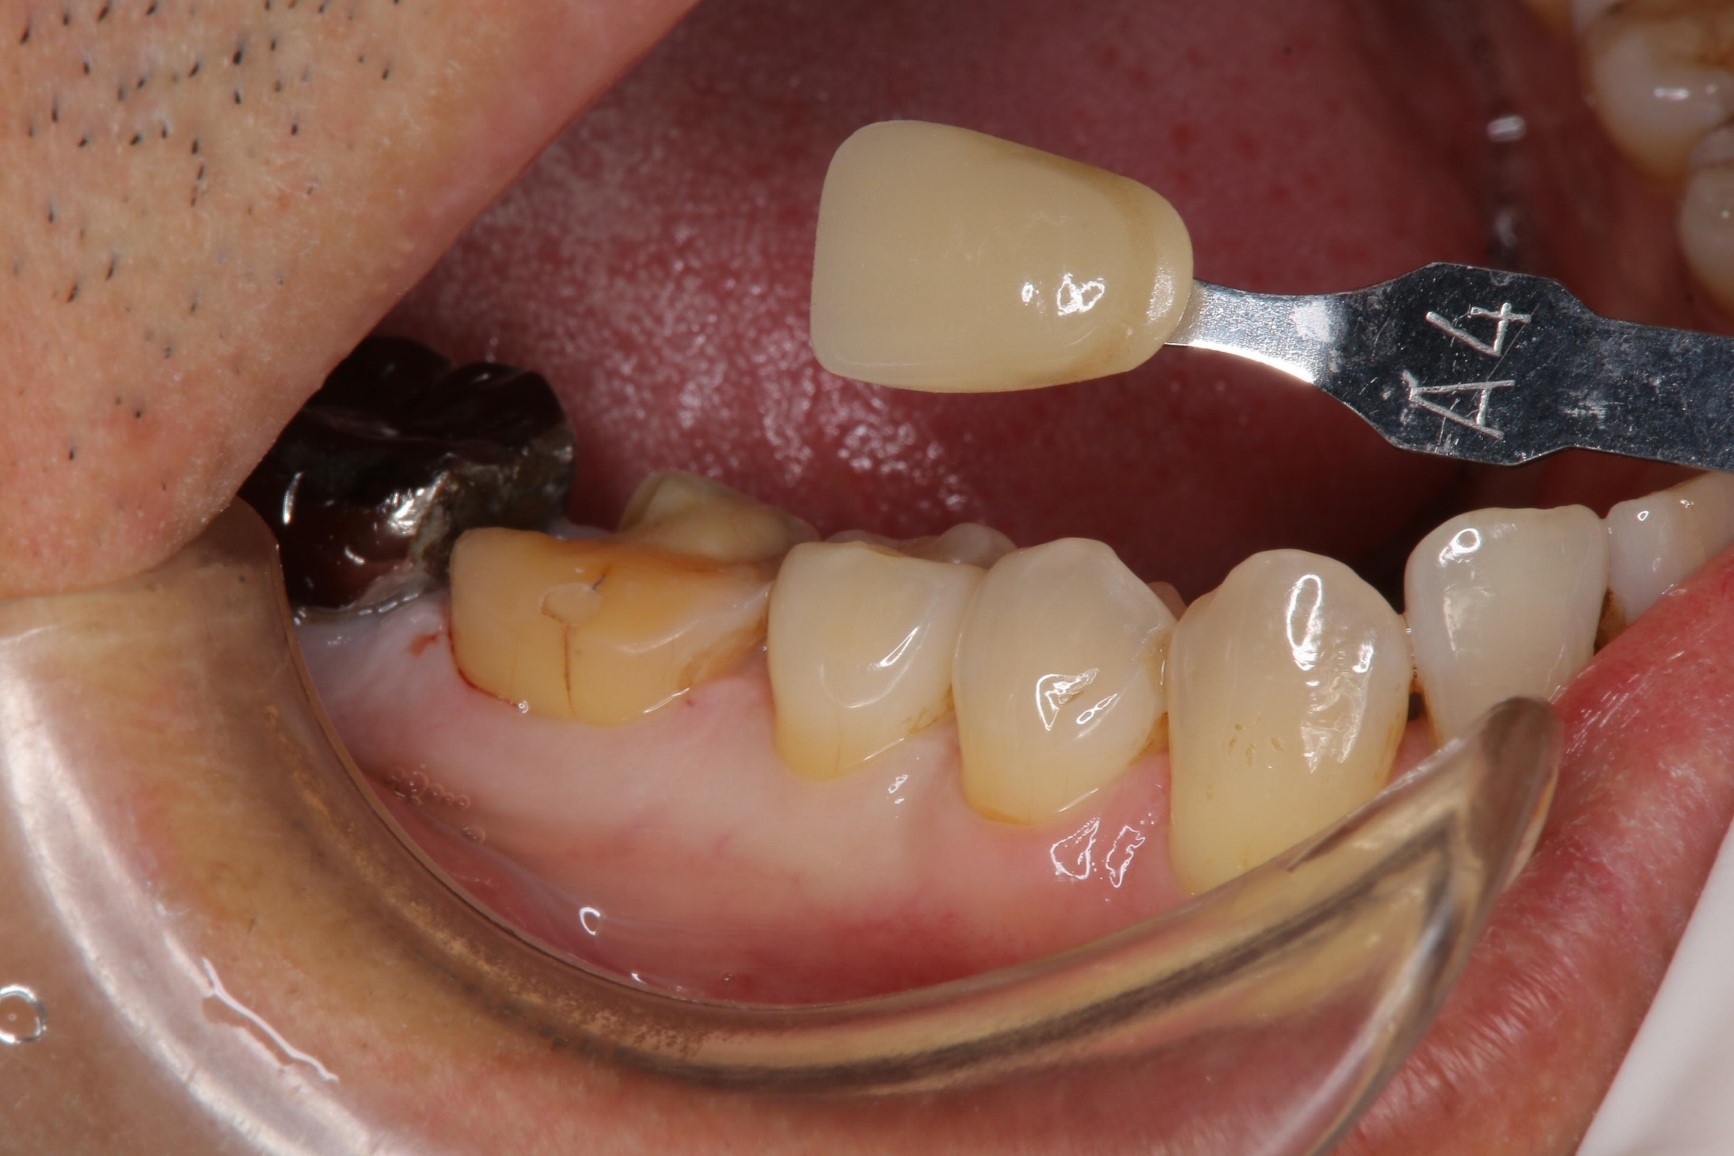

照相比色